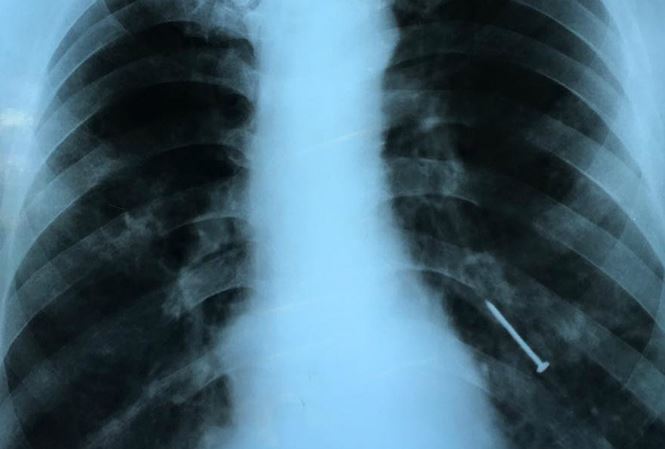

10/07/2018 16:26Người đàn ông bất ngờ bị đinh văng qua miệng xuống phổi

Bác sĩ Phạm Thị Vân Thanh, Khoa Nội soi, Bệnh viện Chợ Rẫy, TP HCM, cho biết bệnh nhân vào viện trong tình trạng ho liên tục 4 tháng, có lúc ho ra máu. Kết quả chẩn đoán hình ảnh phát hiện dị vật nằm ở phế quản thùy dưới bên trái.

Bác sĩ đã nội soi bằng ống mềm gắp thành công dị vật là cây đinh đã gỉ sét khỏi phế quản bệnh nhân. Nếu để lâu, dị vật có thể gây viêm phổi, áp xe phổi, giãn phế quản, ho ra máu. Cây đinh bị gỉ sét nên có thể gây uốn ván. May mắn bệnh nhân chưa bị uốn ván, chỉ viêm phổi nhẹ và có thể tự hết sau khi lấy dị vật.

Bệnh nhân cho biết hoàn cảnh khó khăn, đi biển sửa tàu thuê. Cách đây 4 tháng ông trong lúc đóng đinh vào thân tàu, ông há miệng và không ngờ cây đinh văng vào miệng rồi chui vào phế quản. Từ đó ông ho liên tục nhưng không có tiền đi viện. Gần đây tình trạng ho chuyển nặng, nhiều lúc ho ra máu nên ông mới vào bệnh viện thăm khám.